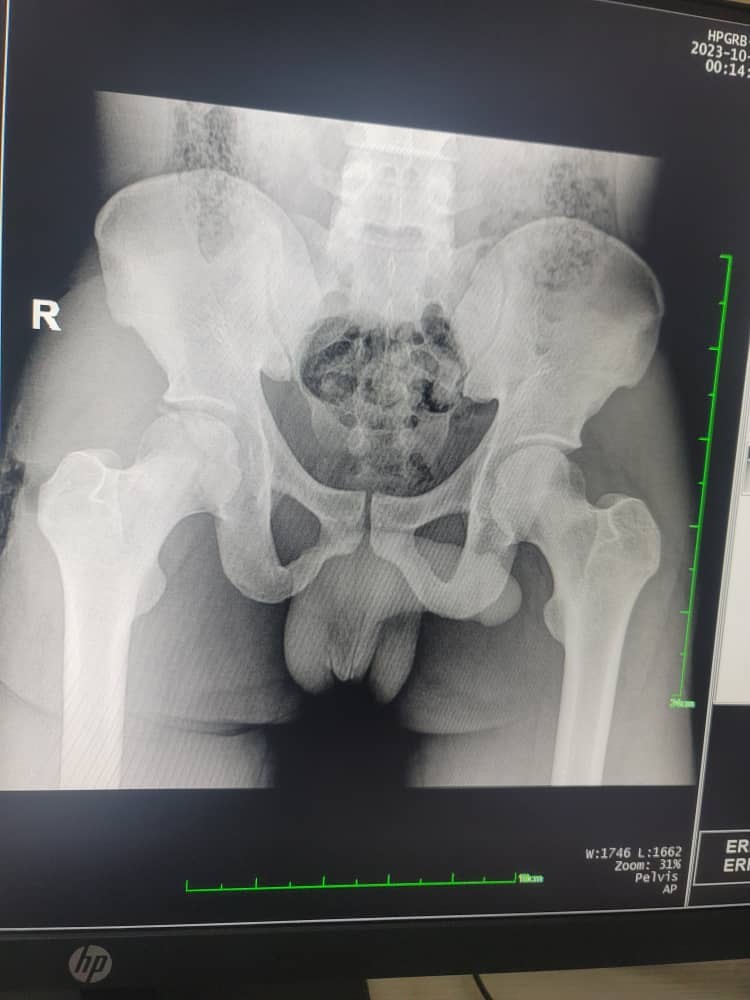

Radiographs of the pelvis and right arm confirmed bilateral hip dislocations with an associated fracture of the inferior acetabular margin of the right hip (Fig. 2).

Figure 2: Initial X-ray.